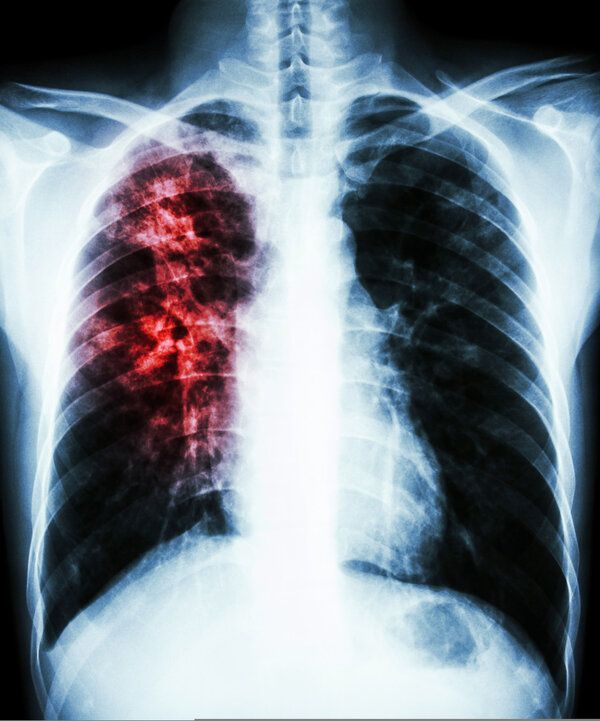

肺结核患者不适宜食用人参果。

人参果是一种温性的水果,肺结核患者食用后可能会导致体内热邪旺盛,从而引起痰火上扰、阴虚火旺等病症,不利于疾病的恢复。因此,肺结核患者不宜食用人参果。

对于肺结核患者而言,饮食调理是辅助治疗的重要环节之一,但并不能代替正规的医疗管理。建议患者在医生指导下接受规范化抗结核药物治疗,并定期复查以监测病情变化。